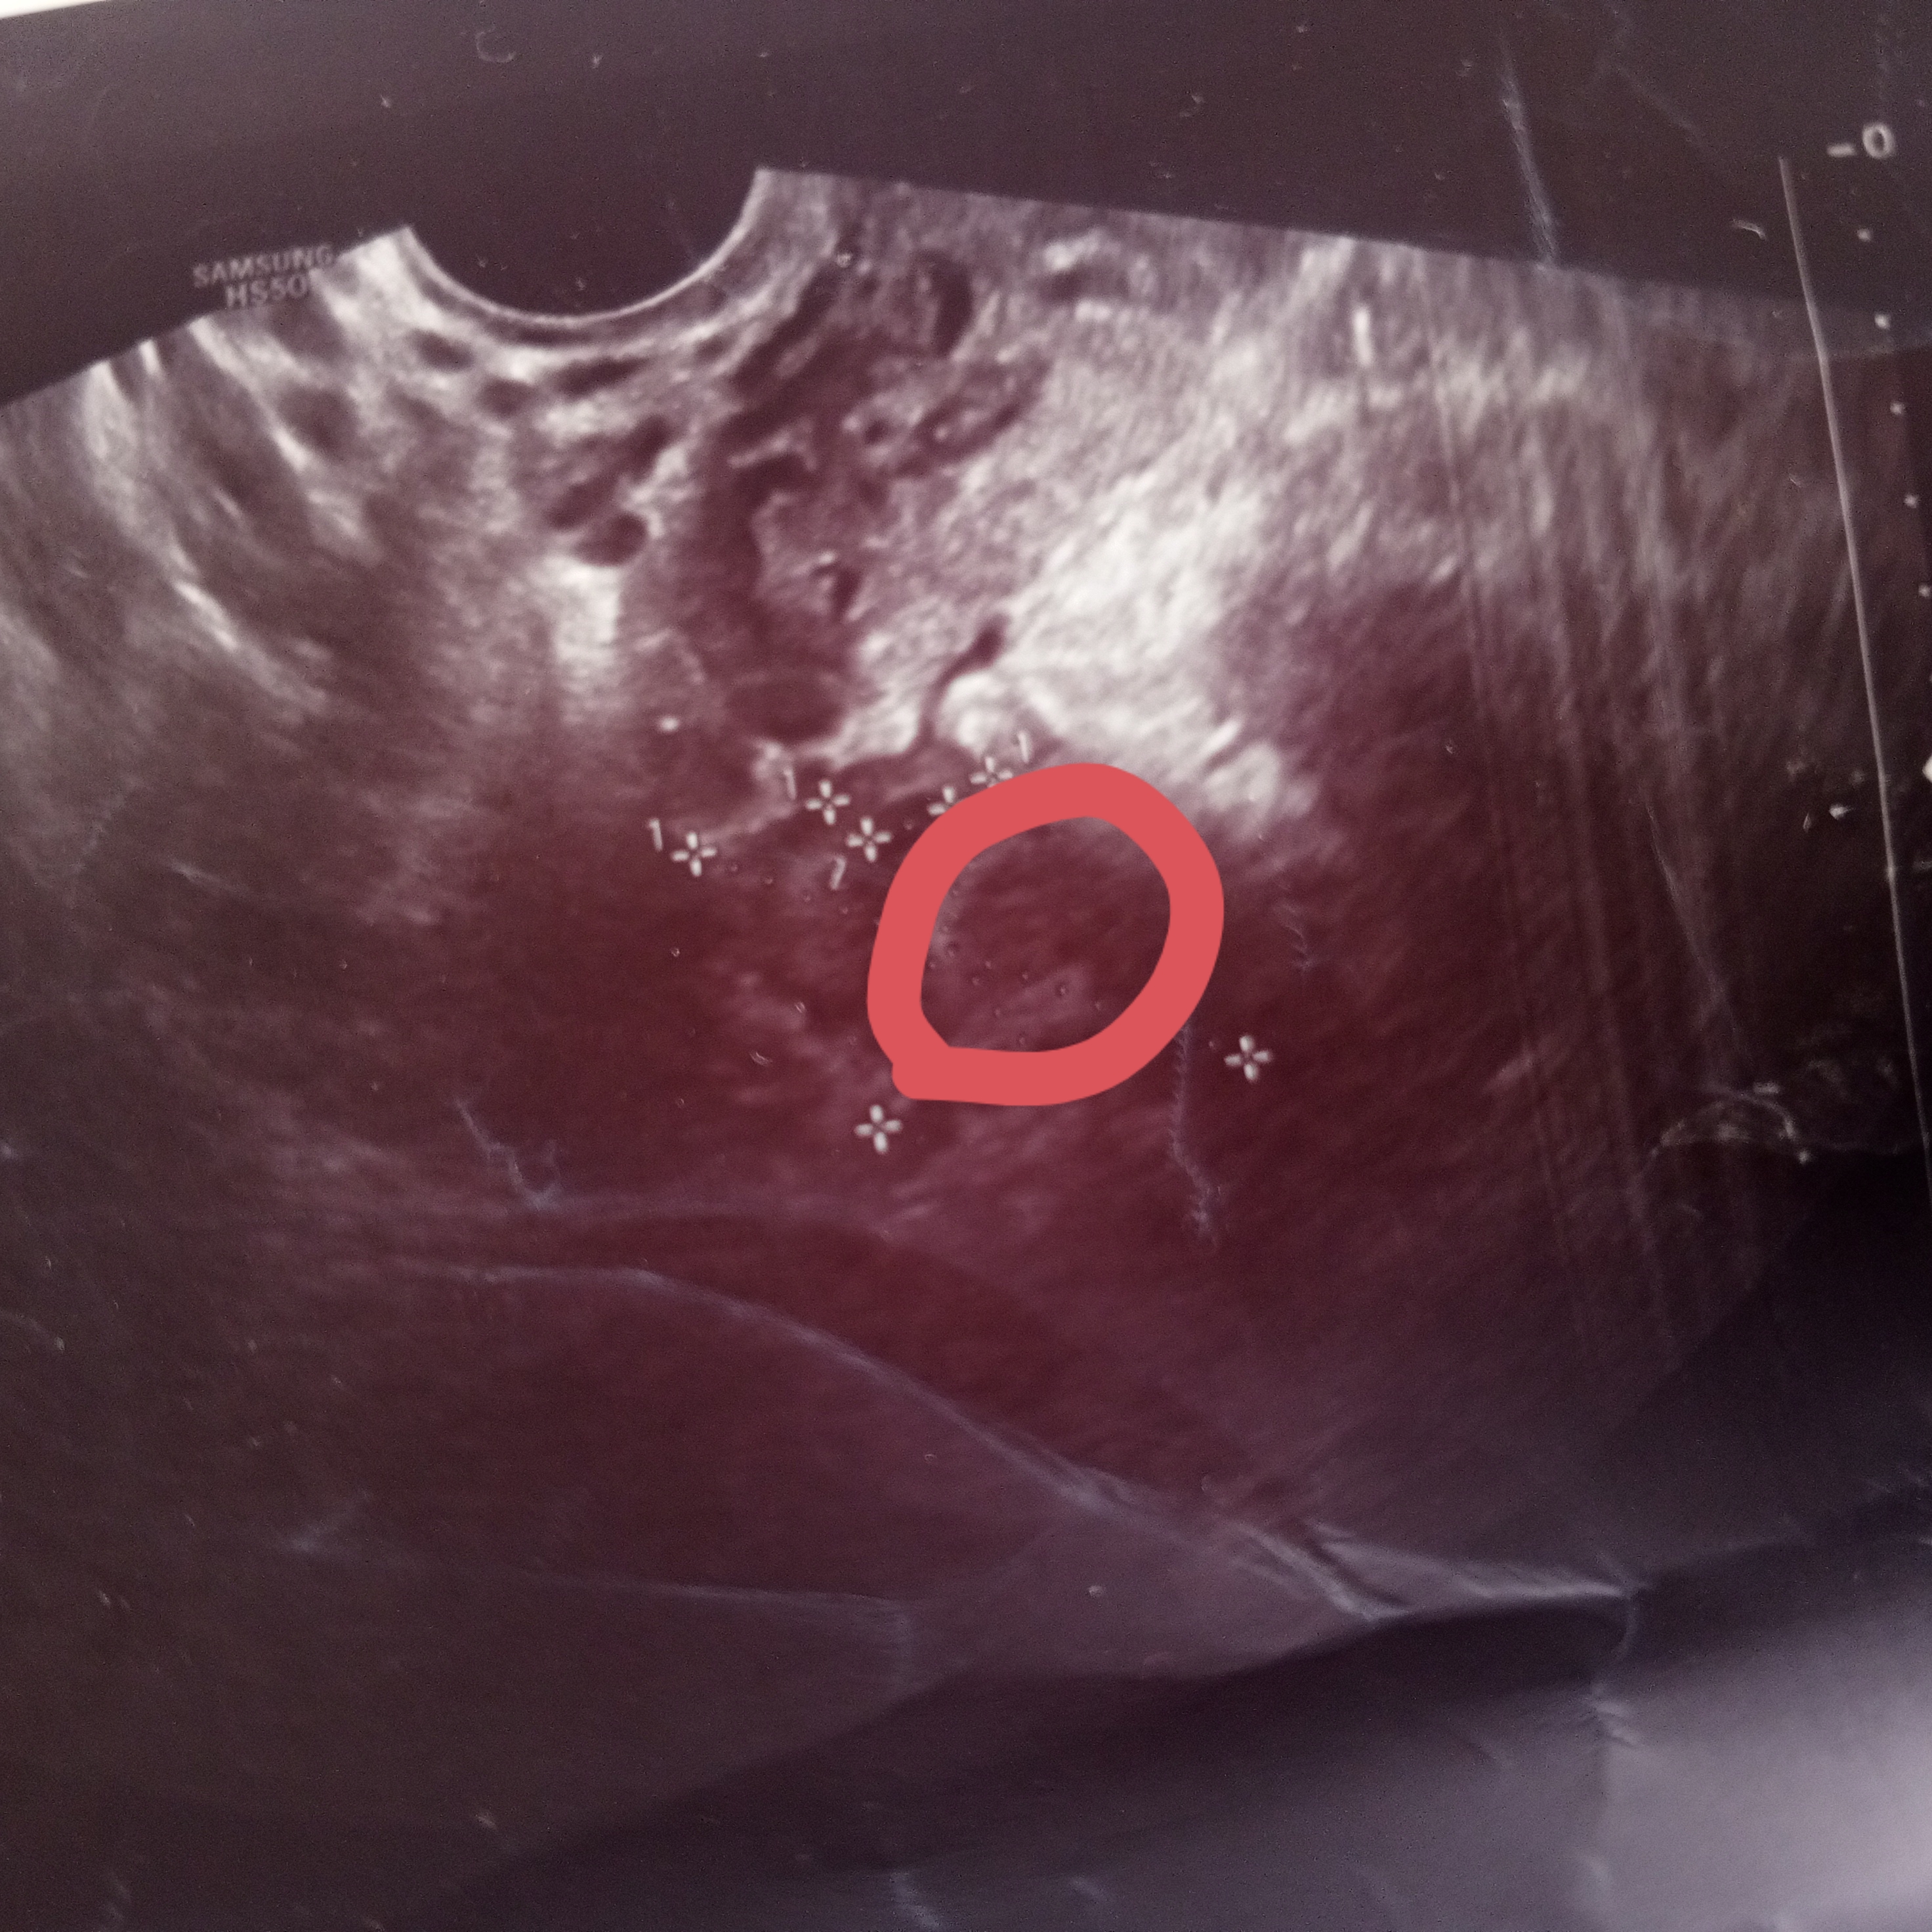

Девочки, сегодня на контрольное узи поеду, жт в ля но в правом посмотрите, я отметила, это не может быть жт? На 1 фоте обвела, второе оригинальное На фолликул не похоже так как он на узи черный а это как то выделяется